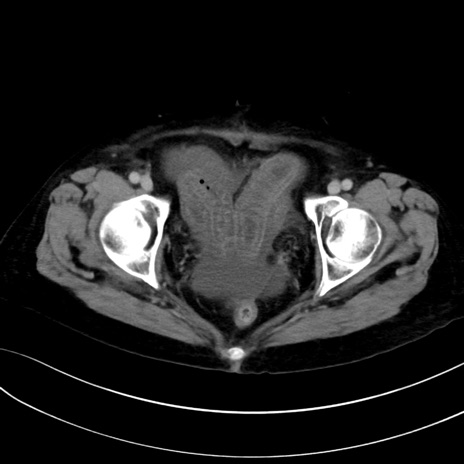

症例13 CT(横断像)1日半後